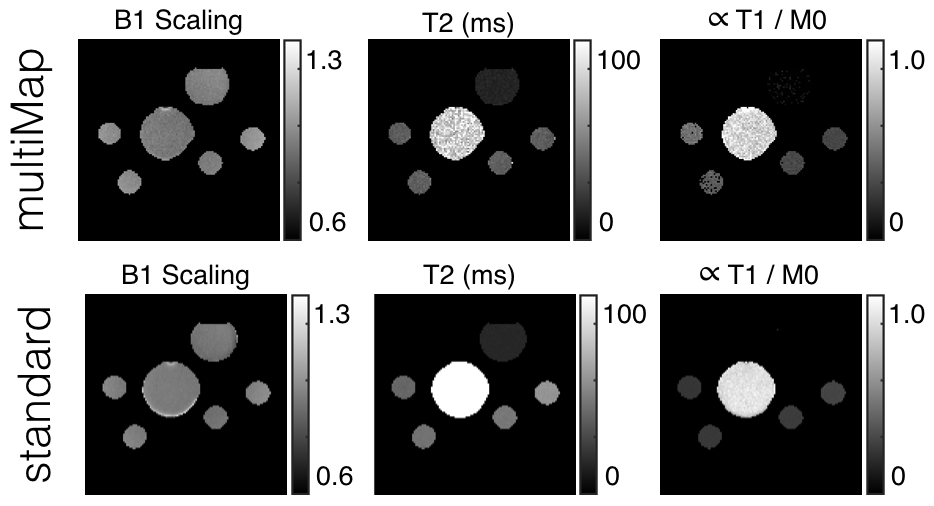

We present the estimates of , , and attained with multiMap to those of standard scanning methods in Fig. 5. Data was collected for each standard quantification individually. A double angle mapping sequence was used to measure B1 [7]. An exponential decay was fit to a series of data collected from a spin-echo sequence with different echo times to estimate . A five-parameter model was fit to data from an inversion recovery sequence according to [17] in order to estimate . The figure shows good agreement for each quantity. The estimate of of bottle is lower than the true value; this is due to the small length of time of the imaging pulse and the acquisitions , , and . In order to estimate longer values, one would need to spread out the acquisitions; this would come at a cost of reduced fidelity for smaller estimates.